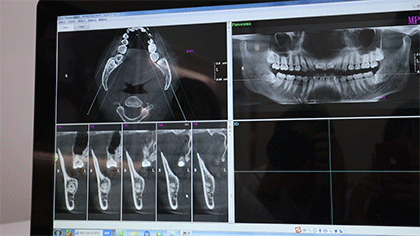

采用先进的3D口腔CT检查设备

只要短短1分钟

牙齿的高清照就出炉了

并同步传输到医生电脑

牙齿存在的问题一目了然

拍完口腔全景片,就是医生一对一面诊

主治医生会根据牙片了解你的牙齿情况